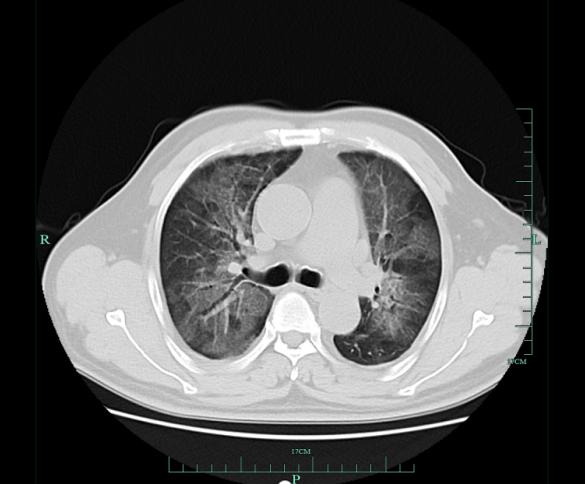

患者的肺部影像

在当地医院做了肺部 CT 检查发现,毛先生双肺大面积变白,当地医院进行抗感染、消炎等对症治疗后,他的病情没有明显改善。当地专家建议他抓紧到对治疗肺部疾病有着丰富经验的浙大一院明确诊断。